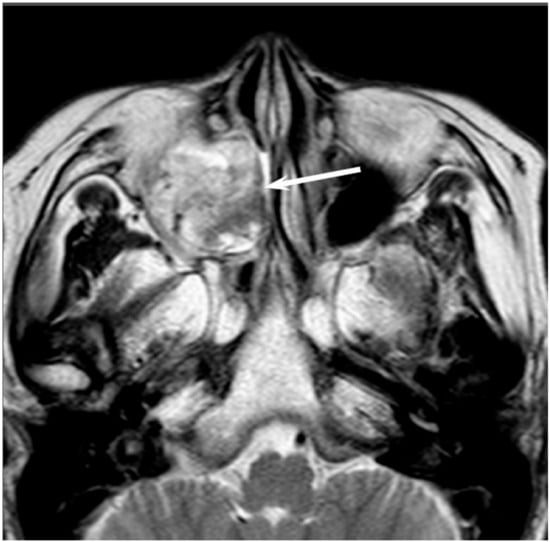

Most SNUCs are larger than 4 cm in maximal diameter at presentation and have ill-defined margins [23]. The aggressive nature of the tumor is reflected in the bone destruction and invasion of adjacent structures, including the paranasal sinuses, anterior fossa, orbit, pterygopalatine fossa, parapharyngeal space, and cavernous sinus [23]. On CT, SNUCs usually appear as a noncalcified mass and show variable contrast enhancement and areas of central necrosis. On MRI, SNUCs show isointensity on T1WI, iso- to hyperintensity on T2WI, and exhibit heterogeneous enhancement on contrast-enhanced T1WI. Owing to the nonspecific imaging findings, it is typically difficult to distinguish between SNUCs and SCCs (Figure 4).

Figure 4. Sinonasal undifferentiated carcinoma of the right nasal cavity. Contrast-enhanced CT image showing an ill-demarcated, heterogeneously enhanced lesion (arrow).